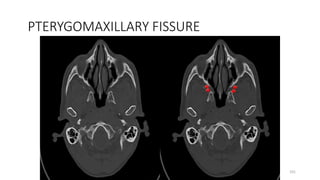

PTERYGOMAXILLARY FISSURE

PTERYGO MAXILLARY FISSURE